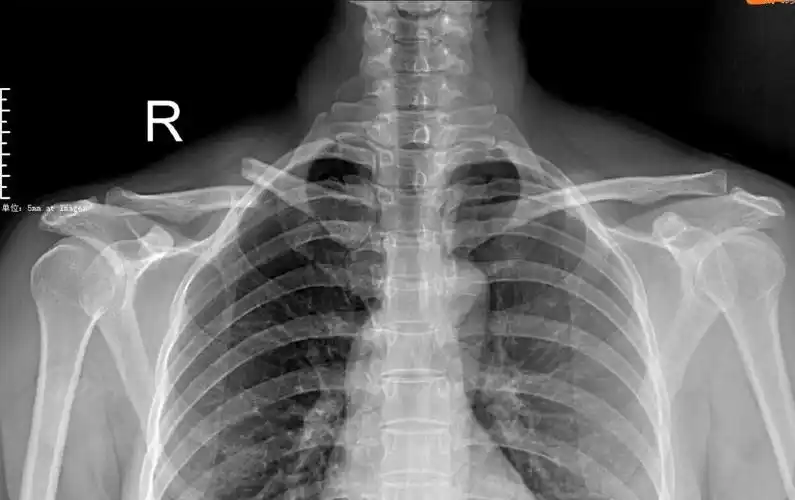

右侧锁骨骨折x线片

右锁骨x线片:右侧骨折